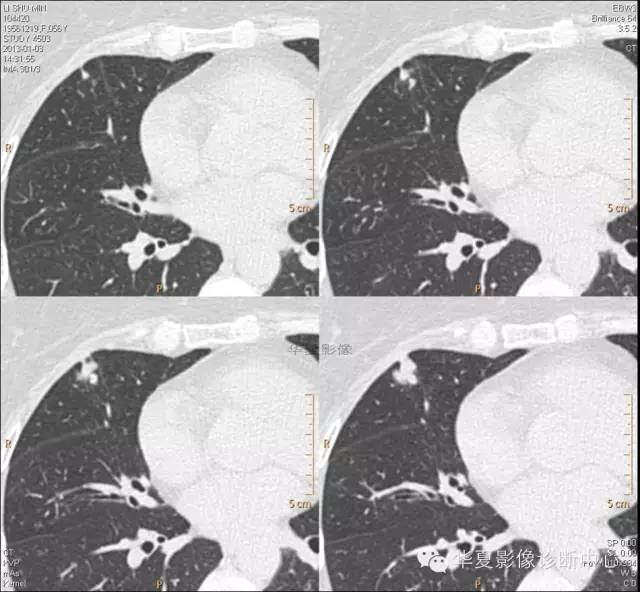

【病例学习】典型周围型肺癌CT病例一例

女,56岁,其父因肺癌去世,自觉胸部疼痛不适来诊要求拍胸片。

1.右肺上叶:肺组织1块,大小13×4×7cm。切面棕红色。2.右肺上叶肿物:灰白色组织一块,大小3×1×1.5cm。切面灰白色。3.右肺中叶结节:灰白色绿豆大组织1块。4.淋巴结:灰黑色绿豆大组织1块。

(右)肺中分化鳞状细胞癌。浸及胸膜。支气管残端切净。淋巴结未见癌转移(0/10)。